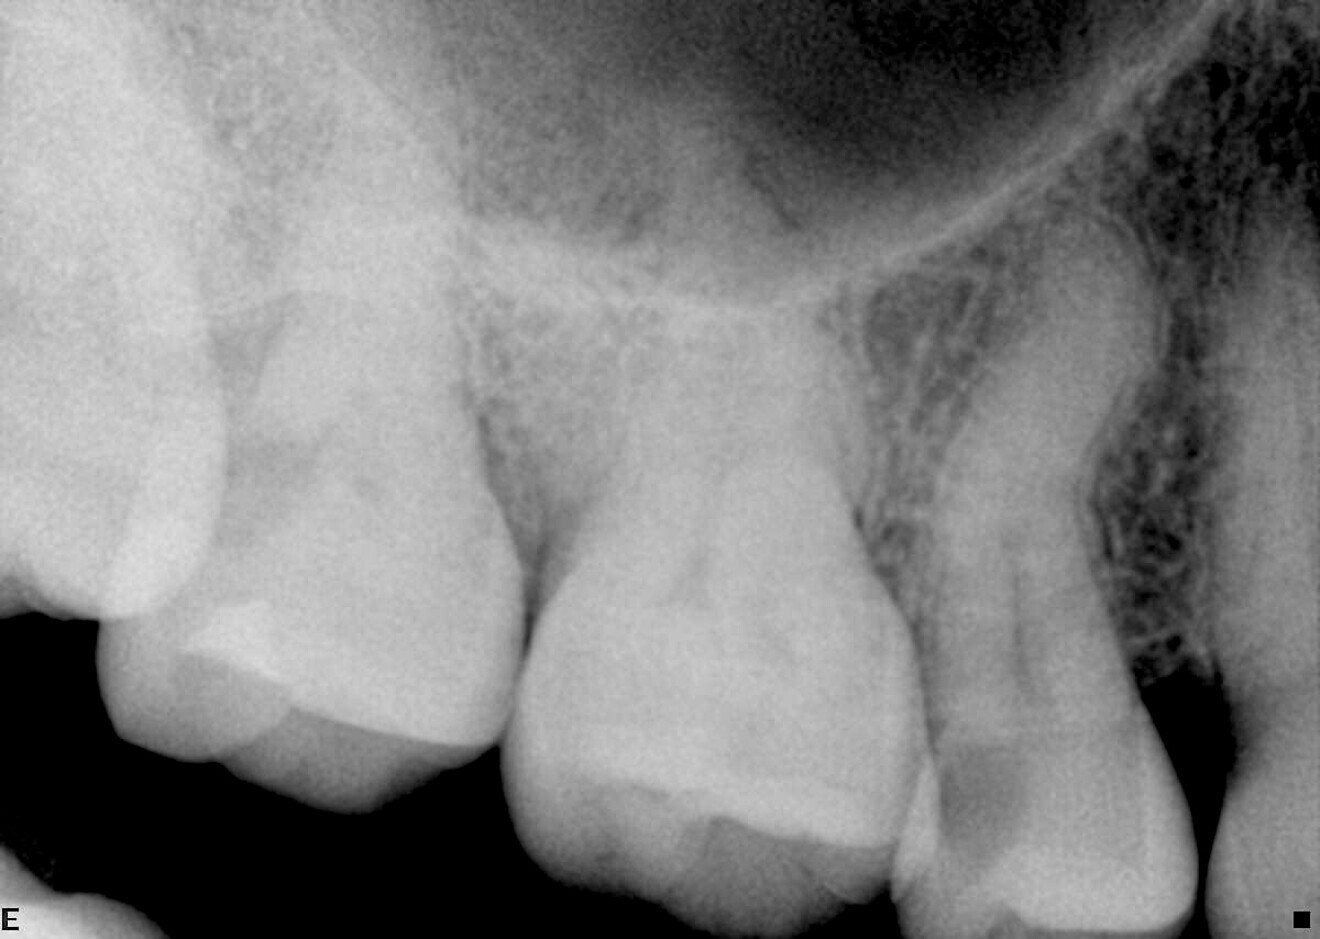

The first case presents two different root canal treatments—of a premolar and a molar—in the same patient, both indicated owing to deep caries and irreversible pulpitis. Surprisingly, the premolar proved more challenging than the molar.

The preoperative radiograph of the premolar offers insight into the complex anatomy and multiple curvatures of the canals (Fig. 4). Two distinct canals are visible, yet they are so closely positioned that they could easily be misinterpreted as one. On the postoperative radiographs, the different apical foramina are clearly identifiable (Figs. 5 & 6). The images also show how well the file respected the original canal anatomy—shaping without excessive coronal enlargement to accommodate the multiple curves. No ledge formation or apical transportation had occurred.

In this case, the 13/0.04 ZenFlex CM file was used as a pre-shaping instrument in the premolar after the orifice opener (Traverse, Kerr Dental). The rest of the sequence followed smoothly in continuous rotation. Both the orifice opener and the 13/0.04 file are part of the pre-shaping concept.

The molar was shaped using the same sequence, though the 13/0.04 file was not required. After using the orifice opener, shaping proceeded directly with the 17/0.04 ZenFlex CM file, followed by the rest of the files in the sequence.

Case 1—Fig. 4: Initial periapical radiograph.

Fig. 5: Post-op periapical radiograph.

ig. 6: Post-op periapical radiograph, angled view.